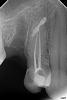

makdoc@bk.ru Опубликовано 14 декабря, 2010 Поделиться Опубликовано 14 декабря, 2010 Доброго вемени суток всем помогите пожалуйста определить что с моим зубом ,врач у которого я была сказал удалять, без мотивации... я не хочу. что с этим делать ???помогите!!! Ссылка на комментарий

DokDent Опубликовано 14 декабря, 2010 Поделиться Опубликовано 14 декабря, 2010 Доброго вемени суток всем помогите пожалуйста определить что с моим зубом ,врач у которого я была сказал удалять, без мотивации... я не хочу. что с этим делать ???помогите!!!Здравствуйте,а какие у вас жалобы,нет ли припухлости на десне над этим зубом и когда удалялся соседний зуб ?Желателно сделать КТ или хотя бы снимок в другой проекции Ссылка на комментарий

Bier Опубликовано 15 декабря, 2010 Поделиться Опубликовано 15 декабря, 2010 странный снимок, мне даже кажется, что это белое пятно какой-то артефакт...попробуйте сделать еще один. Ссылка на комментарий

makdoc@bk.ru Опубликовано 15 декабря, 2010 Автор Поделиться Опубликовано 15 декабря, 2010 +1 делали четыре раза везде одно и тоже ,припухлости нет зуб этот под опору под мост хочу металлокерамику ,не болит не беспокоит ,просто в клинике где я была удаляют нервы из опорных зубов... Ссылка на комментарий

anastasiya.barhatova Опубликовано 15 декабря, 2010 Поделиться Опубликовано 15 декабря, 2010 Скорее всего несколько лет назад у Вас был перелом корня в верхней трети (ушиб), без разрыва сосудисто-нервного пучка (я так поняла, зуб внешне - не отличается от здоровых зубов: по цвету, длине ?)Со временем произошло сращение корня и образование мозоли (белая линия).В любом случае, удалять зуб - не стоит! Пролечить эндодонтически,если верхнюю треть корня пройти не удастся - сделать резекцию. Ссылка на комментарий

silver77 Опубликовано 16 декабря, 2010 Поделиться Опубликовано 16 декабря, 2010 предположительно-это артефакт от лечения удаленного зуба,который накладывается в проекцию 2.5 зуба Ссылка на комментарий

Dr. Surkin Опубликовано 16 декабря, 2010 Поделиться Опубликовано 16 декабря, 2010 скорее всего это остаток пломбировочного материала, вышедшего из 5-го, которого уж нет.На прогноз 4-ки вряд ли влияет. Ссылка на комментарий